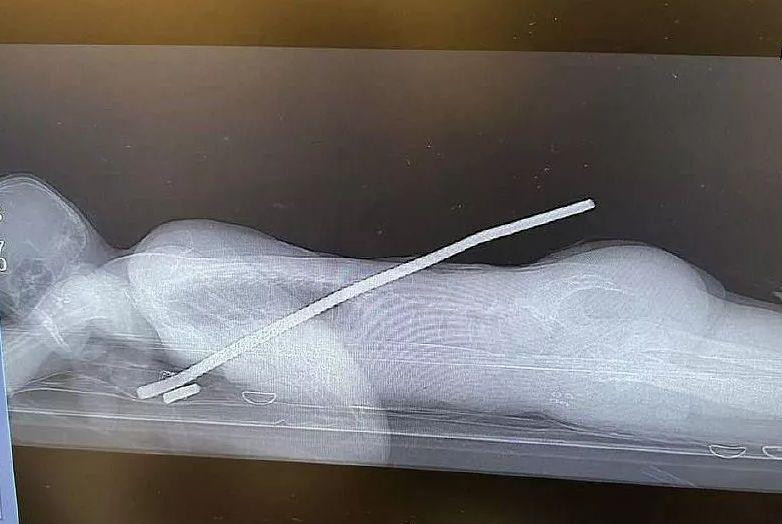

Как сообщил министр здравоохранения Краснодарского края Евгений Филиппов, мужчина упал со второго этажа на кусок арматуры. При падении металлический прут буквально проткнул пострадавшего насквозь, однако задел только правое легкое. Врачи городской больницы №4 провели обследование с применением различных инструментальных и лабораторных инструментов. Оказалось, что задето только легкое. Мужчине требовалась экстренная операция. Уже в операционной у пациента срезали часть арматуры, что должно было облегчить извлечение инородного предмета.

При этом главной особенностью процесса стало то, что хирурги «выключили» на время оперативного вмешательства поврежденное легкое. После извлечения куска металла орган был «подключен» к системе жизнедеятельности. Операция продолжалась в течение 2 часов. Пациент уже находится в сознании и чувствует себя хорошо.

По информации издания «Кубанские новости», мужчина упал на арматуру 29 июля. Пострадавшим оказался местный житель 38 лет. Спасатели использовали для перерезания металлических прутьев гидравлический инструмент. Врачи в это время находились поблизости и уже оказывали потерпевшему первую помощь